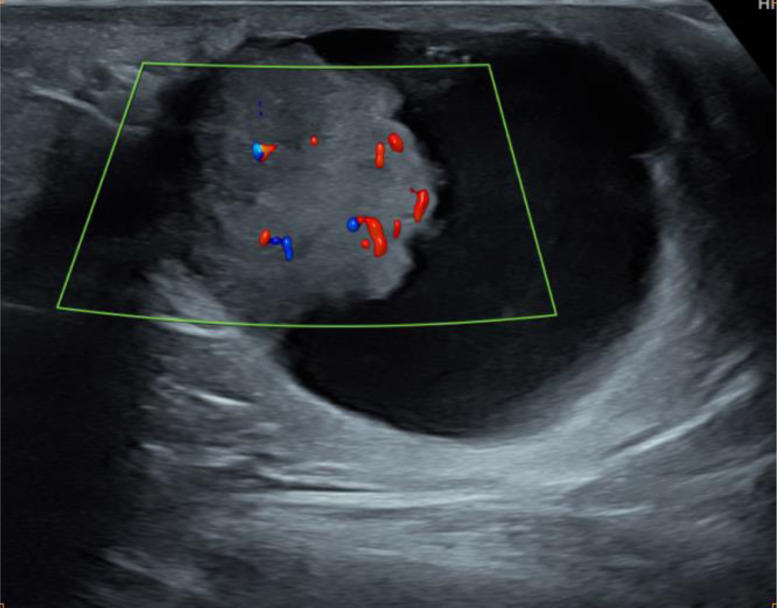

Ultrasonography was first performed showing a supernumerary breast tissue, of left axillary location, with a complex cystic mass containing an echogenic-anechoic liquid level, and a tissue component, that appears hyperechoic, with ill-defined margins, homogeneous (Fig. 2), with vascular pedicle in color Doppler (Fig. 3) and hard elasticity in ultrasound elastography (Fig. 4).

Fig. 3.

Ultrasound of the left axilla showing Doppler vascularization of the tissue component.